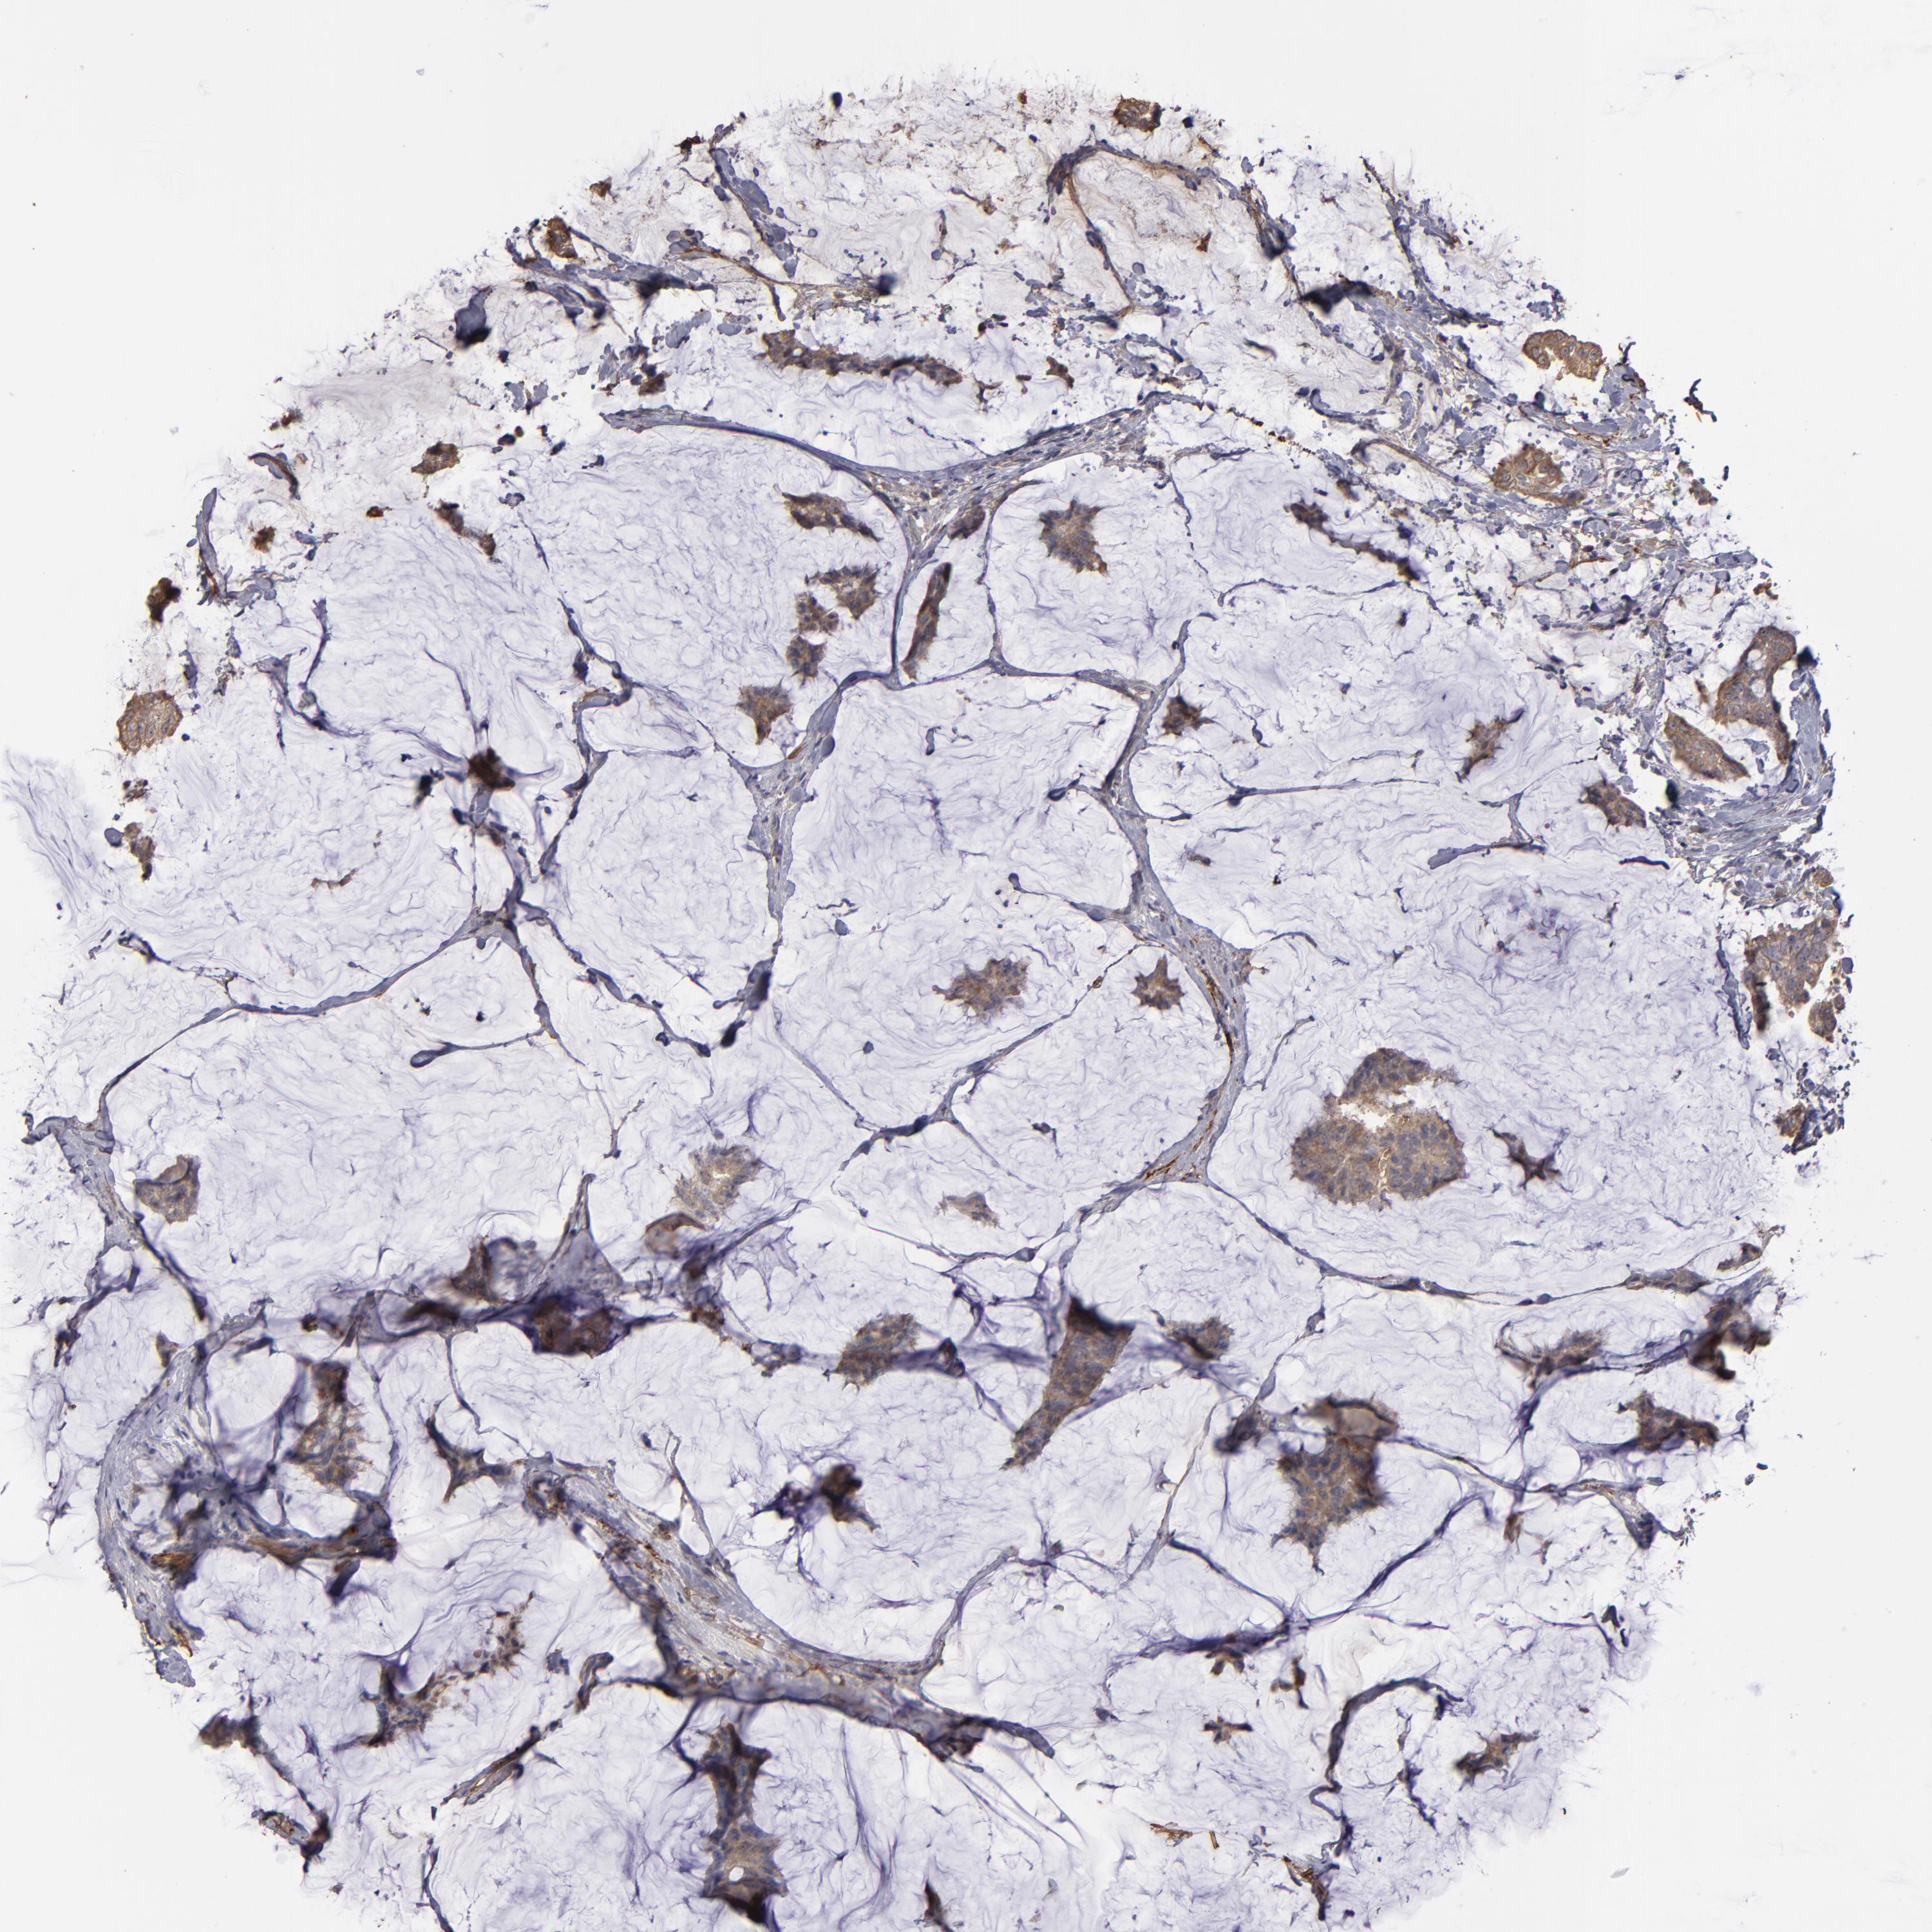

CANCER BREAST CANCER Show tissue menu

BRCA TCGA BRCA VALIDATION PROTEIN EXPRESSION